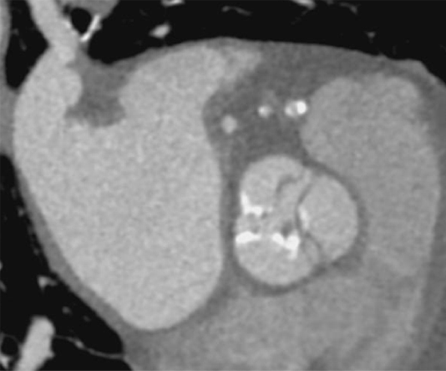

TAVI後の血栓弁の評価です。TAVI後のCTで弁葉に低吸収域を認める症例を見かけますが、

この所見はHALTと呼ばれ、人工弁に付着した血栓と考えられています。

HALTが大きい症例では弁葉の動きを障害することがあるため、CTでの評価は重要です。

HR82の高心拍で、モーションアーチファクトの影響が強かった症例です。

SSF2.0でも金属からのアーチファクトは少し残存していますが、モーションアーチファクトが抑制され、

SSF2.0 Offでは見えずらかった弁葉のわずかなlow densityをSSF2.0ONではしっかりと確認できるようになりました。